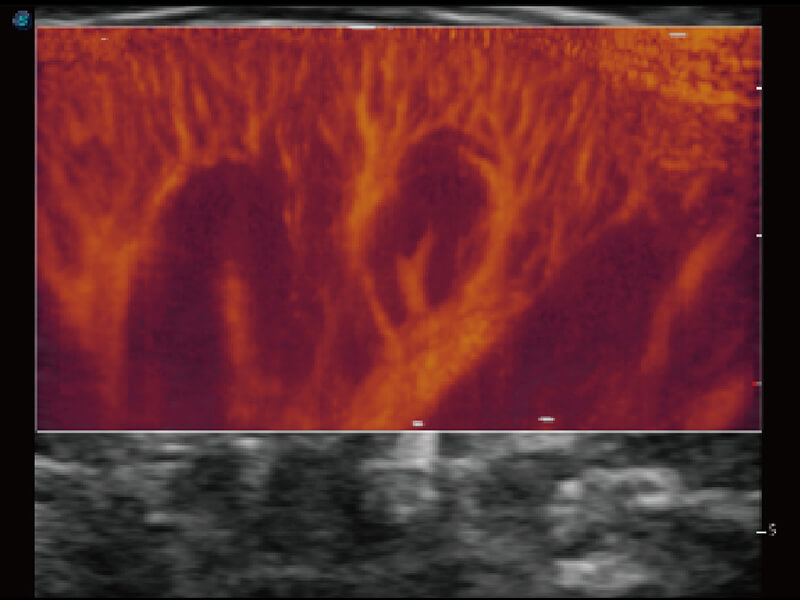

成像功能

S60探头工艺,从前端信号处理每一个环节采集无损声学数据,真实还原组织原貌,再现解剖细节。

超宽频带技术,为容积成像带来优质的二维图像基础,为您呈现丰富的结构细节,栩栩如生地展示宝宝的宫内形态以及各种组织的立体结构。